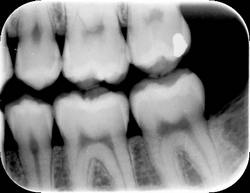

However, the human eye is only capable of distinguishing 32 shades of gray, which corresponds to a spatial frequency ranging from 5 to 7 lp/mm without magnification. The question then becomes, does the magnitude of a digital system spatial resolution above about 10 lp/mm make any diagnostic difference in the clinician’s ability to recognize pathosis radiographically? The answer is still being debated, but at least from our viewpoint, which can be supported from some of our initial investigations into this question, 1,2 probably not. Therefore as an example, can dentists recognize carious lesions confined to enamel as well using digital images as compared to radiographic film? Probably so, but further investigation is needed. An example of an image taken with a Soredex OpTime (spatial resolution of 12.5 lp/mm) is shown in Figure 1. An arrow is pointing to noncavitated proximal carious lesions.